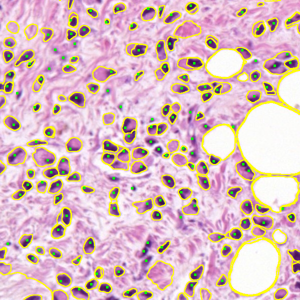

Dataset 2, released as supplementary material in [73], contains 36 digitized H&E-stained microscopy images (600 × 600 pixels) with 7931 nuclei annotated by three expert pathologists; only consensus annotations are retained. It is designed for cell nuclei detection.

Representative samples from the three datasets are shown in Fig. 1. In (a), the first frame of the synthetic video in Dataset 1 illustrates the strong illumination gradients produced by distance-dependent shading together with orientation-dependent interactions between vertex normals and the light direction. The H&E images in (b) and (c), also from Dataset 1, depict a mast cell infiltrate from a patient with non-alcoholic steatohepatitis and cirrhosis and, respectively, a sample from a patient with sclerosing polycystic adenosis of the parotid gland; the former consists primarily of purple nuclei, white cytoplasm, and pink extracellular tissue. Subfigures (d) and (e) show two examples from Dataset 2 accompanied by their ground-truth nuclei annotations, while (f) and (g) present a representative image from Dataset 3 together with its corresponding cell mask.

Figure 1: Samples from Datasets 1–3. (a) First frame of the 74-frame video in Dataset 1 (1770 × 880) with a superimposed red mesh. (b,c) H&E-stained tissue images from Dataset 1 (1000 × 750; 950 × 730). (d,e) Cell images from Dataset 2 (600 × 600) with nuclei annotations. (f,g) Image from Dataset 3 (512 × 512) with annotation.

7.2 Quantitative Results

We now assess SP using the 36 images from Dataset 2 and 50 images from Dataset 3. In our evaluation, we employ the Dice similarity coefficient (DSC) (as usual defined as the harmonic mean of precision and recall), DSC=2/(1/precision+1/recall),\mathrm{DSC}=2/(1/\mathrm{precision}+1/\mathrm{recall}), precision=tp/(tp+fp),\mathrm{precision}=\mathrm{tp}/(\mathrm{tp}+\mathrm{fp}), recall=tp/(tp+fn),\mathrm{recall}=\mathrm{tp}/(\mathrm{tp}+\mathrm{fn}), where tp\mathrm{tp} denotes the number of ground-truth points within the segmentation foreground, fp\mathrm{fp} the number of predicted regions without ground truth, and fn\mathrm{fn} the number of ground-truth points outside the segmentation foreground [73]. In Dataset 3, since pixel-level annotations were given [74], the above metrics were calculated on a per-pixel basis.

Table 1, on Dataset 2, shows that SP obtained the highest DSC (88.78), which is higher by 5.90, 7.09, 8.31, and 22.46 compared to SAM, ZZ, SMST, and AR, respectively. The segmentation time of SP was 14.55s, approximately twice that of SAM (the second fastest method without considering pre-processing times), and more than one order of magnitude lower than the level-set methods AR and ZZ. While AR and ZZ need user-specific markers as input (the pre-processing time indicated as \infty), SAM needs to load the pre-trained model (6.09s) while SP and SMST need to generate the superpixels in the pre-processing step (0.08s). Figure 11 shows the resulting segmentations for two example images from Figs. LABEL:fig_sub:he3_image and LABEL:fig_sub:he4_image from Dataset 2. The segmentations reflect the trends observed in Table 1, with SP achieving the highest DSC and segmentation times exhibiting a similar relative order.